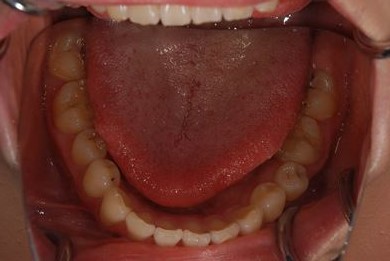

治療後

• 治療後